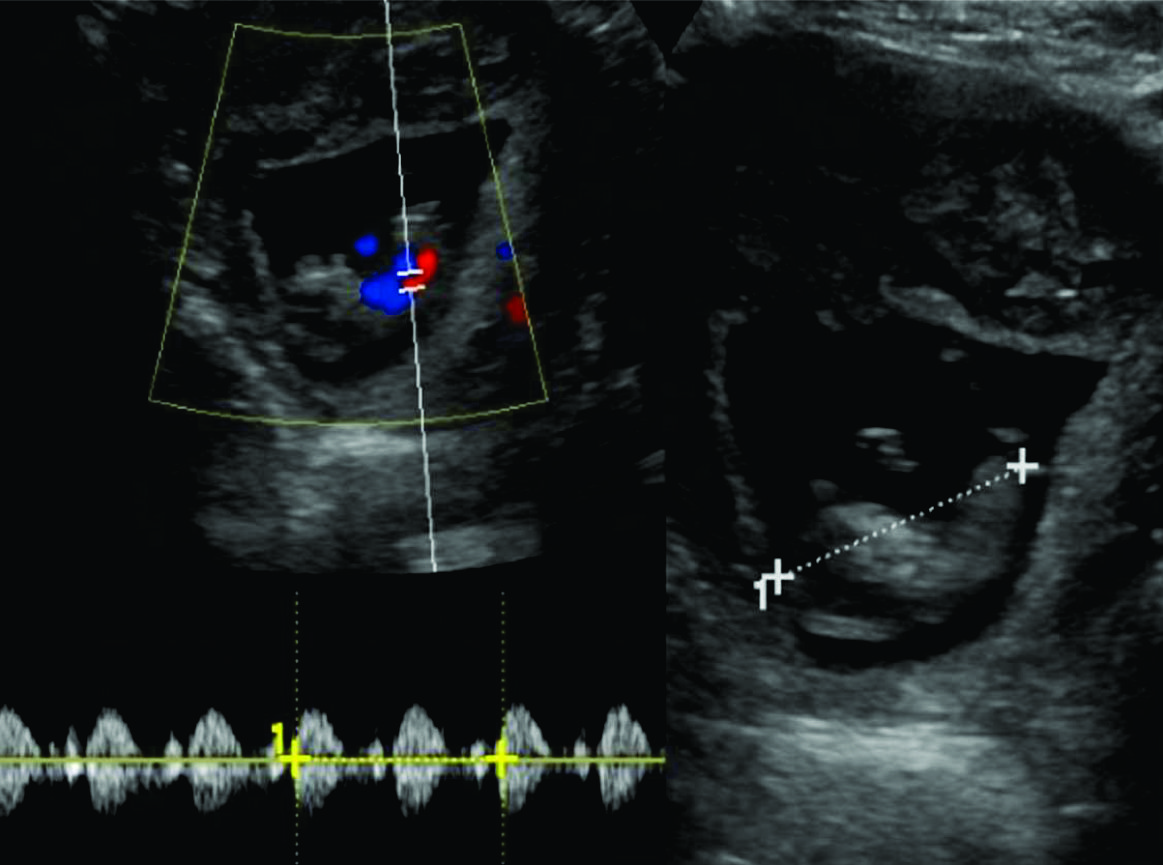

Estos embarazos ectópicos cervicales deben distinguirse del aborto cervical, que ha sido definido como un aborto espontáneo de embarazo intrauterino en el canal cervical donde se retiene el aborto por un orificio externo resistente. (3) El saco gestacional de un aborto en cuello uterino es a menudo descrito como crenado (4), será redondo u ovalado y por lo general demuestran alguna evidencia de un feto o saco vitelino. E l or i f i c io int e rno inv a r i abl ement e s e di - lata en un aborto cervical y está completamente cerrado en un embarazo ectópico cervical. Las cavidades endometriales en un aborto cervical a menudo muestran una masa ecogénica densa que representa una mezcla de sangre y productos de la concepción, mientras que en el embarazo ectópico cervical solamente presenta un endometrio prominente causado por reacción decidual (3). (figura 3)

Todas las pacientes presentaban criterios diagnóstico de embarazo ectópico cervical: a) útero vacío, b) cérvix en forma de tonel, (figura 3, a yb) c) saco gestacional presente debajo del nivel de las arterias uterinas, El diagnóstico es más fácil con la presencia de actividad cardiaca en el cérvix, lo cual excluye el aborto cervical.

Figura 3

a y b) Transabdominal

c y d) Transvaginal

Se observa embarazo ectópico cervical donde se señala el saco gestacional (flecha fina), y el embrión dentro del saco (flecha gruesa). El endometrio mide 5 mm de espesor, el saco gestacional mide 25 mm de diámetro promedio. El embrión presenta un LCC de 13 mm compatible con gestación de 7 semanas.